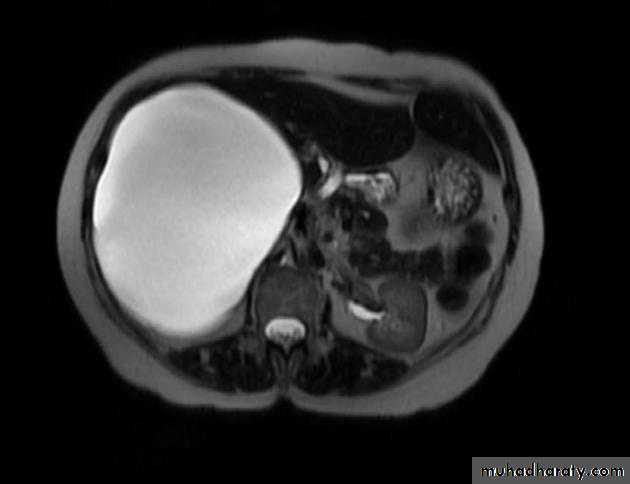

Benign lesions

Hemangioma